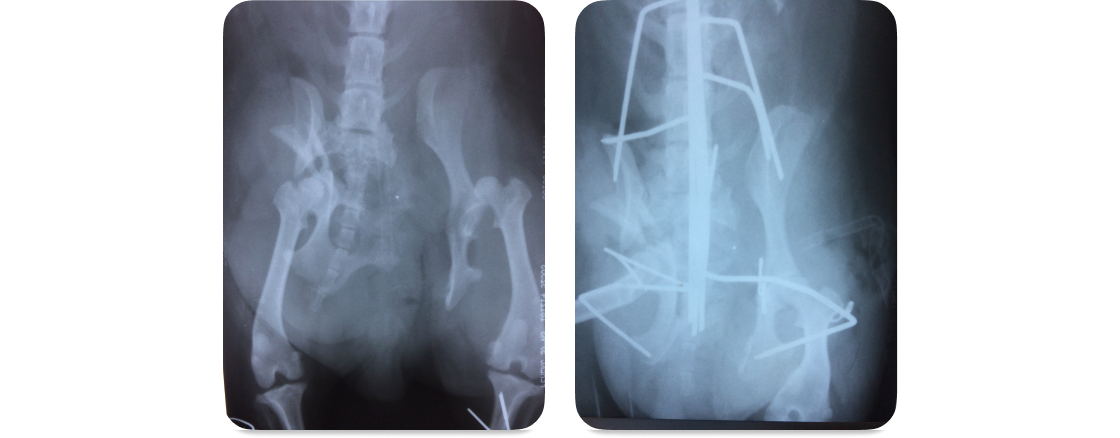

Перелом таза у собаки